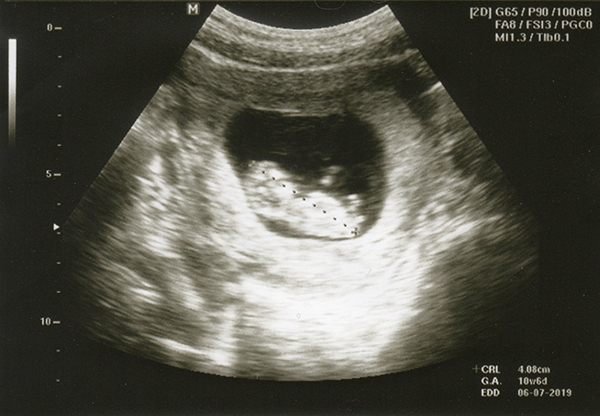

ทันทีที่หมอเอาเครื่องอัลตร้าซาวด์นาบกับหน้าท้องเราก็เห็นตัวน้องเลย

เราคาดอายุครรภ์ผิดไปนิดหน่อยค่ะ หมอบอกว่าน้องอายุ 10 สัปดาห์ ณ วันที่ตรวจอัลตร้าซาวด์ครั้งแรก น้องดิ้นโชว์ด้วยนะคะ